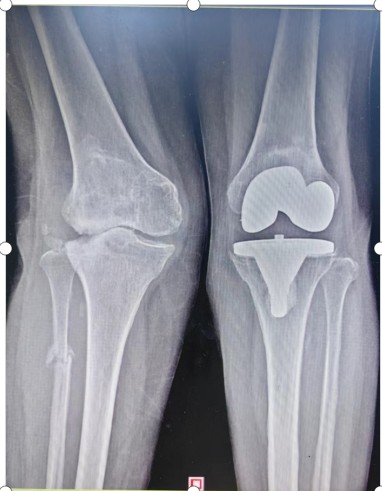

早在2015年,劉奶奶就因左膝關節(jié)重度骨性關節(jié)炎,在衡陽市中心醫(yī)院骨科二區(qū)進行了左膝關節(jié)置換術。2022年6月,69歲的劉奶奶又因右膝關節(jié)疼痛畸形伴行走障礙再次入住骨科二區(qū)。劉奶奶右膝關節(jié)疼痛、畸形嚴重,必須依賴助行器行走。

入院后羅湘平主任醫(yī)師、彭健副主任醫(yī)生及蔣瀟純主治醫(yī)師查體時發(fā)現(xiàn)劉奶奶的右膝關節(jié)重度外翻,內(nèi)側(cè)副韌帶松弛嚴重致膝關節(jié)失去穩(wěn)定性。CT檢查發(fā)現(xiàn)右膝關節(jié)外側(cè)脛骨平臺缺損明顯,深度達1.5厘米以上,長期應力異常,導致腓骨近端應力性骨折。這種復雜膝關節(jié)畸形行人工膝關節(jié)置換不但技術難度大,而且費用很高。根據(jù)劉奶奶膝關節(jié)評估結果,可能需要行鉸鏈膝關節(jié)假體及金屬墊塊充填骨缺損,僅假體材料費用就要達6萬余元,普通家庭無法承受。

術后一年